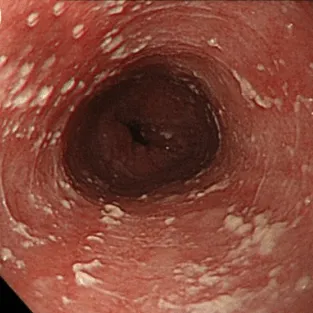

Степень I

Несколько приподнятых белесоватых бляшек размерами до 2 мм в диаметре, с гиперемией, но без отека или язв.